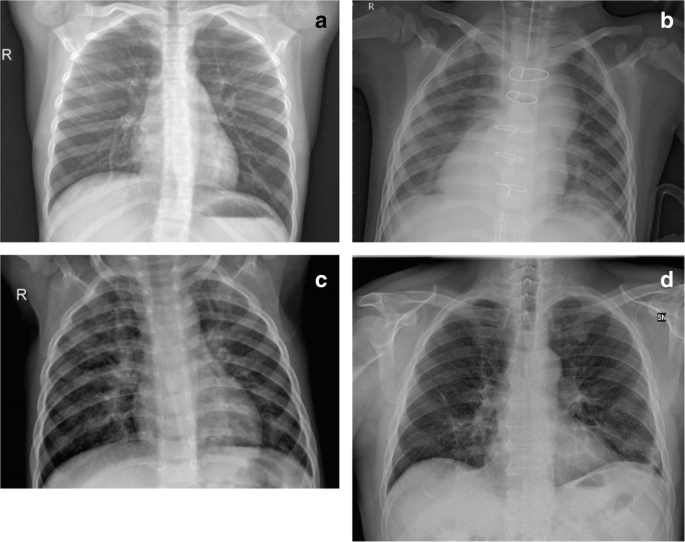

20200417 In general the lung imaging findings of COVID-19 patients are consistent with other viral pneumonias there is no proven specific finding for COVID-19 though there may be suggestive patterns. 20201101 The COVID-19 pandemic has led to an unprecedented surge in hospitalised patients with viral pneumonia. 20210105 The symptoms of COVID-19 pneumonia may be similar to other types of viral pneumonia.

Frontiers Covid 19 Pneumonia In Children From Etiology To Management Pediatrics

Diagnostics Free Full Text Weakly Labeled Data Augmentation For Deep Learning A Study On Covid 19 Detection In Chest X Rays Html

Radiological Findings For Diagnosis Of Sars Cov 2 Pneumonia Covid 19 Medicina Clinica English Edition

Multimodality Imaging Of Covid 19 Pneumonia From Diagnosis To Follow Up A Comprehensive Review European Journal Of Radiology

Covid 19 Radiology Reference Article Radiopaedia Org

Detection Of Covid 19 Using Cxr And Ct Images Using Transfer Learning And Haralick Features Springerlink

Ikonos An Intelligent Tool To Support Diagnosis Of Covid 19 By Texture Analysis Of X Ray Images Springerlink

Diagnostics Free Full Text Artificial Intelligence Applied To Chest X Ray For Differential Diagnosis Of Covid 19 Pneumonia

Covid 19 Pneumonia The Great Radiological Mimicker Springerlink

Chest Ct Findings Of Patients Infected With Novel Coronavirus 2019 Ncov Pneumonia Imaging Technology News